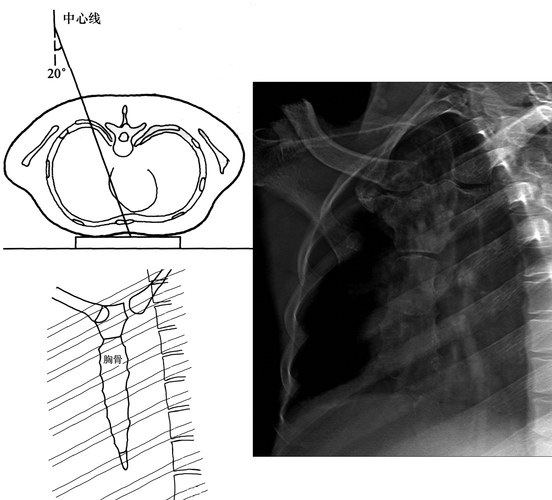

①后前位(posteroanterior view,pa view)投照体位:x线从患者背后穿透

上图为正常胸部后前位片 上图是胸部侧位片的拍摄,一般采取右侧位